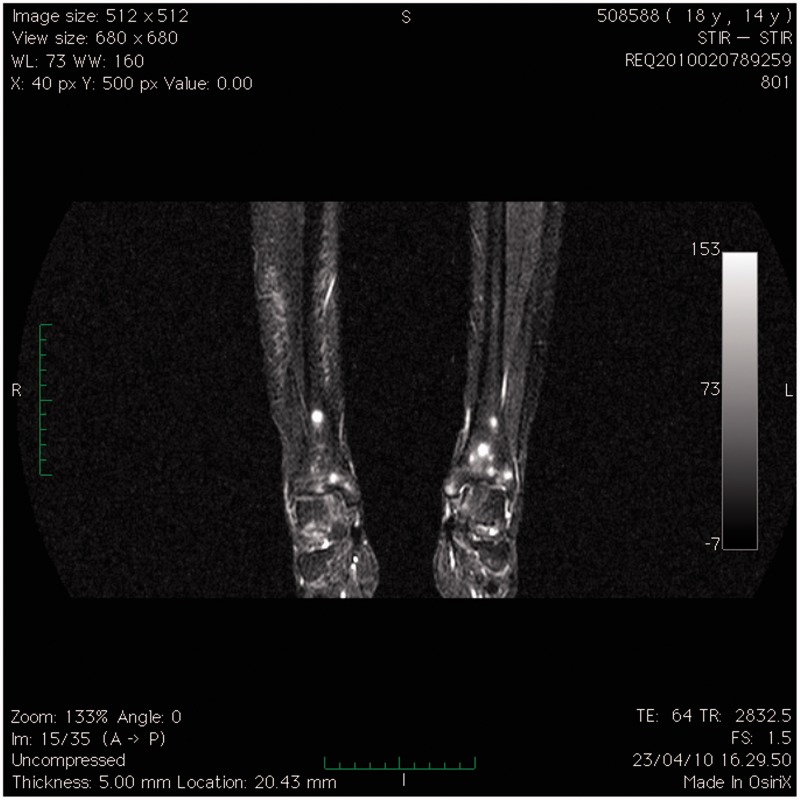

嗜吞噬细胞无原体是一种专性细胞内细菌,是人类粒细胞无原体病(HGA)的病原体,HGA是一种蜱传感染,通常表现为发热、不适、细胞减少、脾肿大和肝炎。在此,我们报告一例14岁的HGA女孩,其全身磁共振成像(MRI)显示了一个不寻常的图像,其特征是小的,广泛的标点毫米结节,t1加权低信号和STIR序列高信号。这一首次报道的发现可能代表了鉴定非典型传染病的另一种工具。

Anaplasma phagocytophilum, an obligate intracellular bacterium, is the causative agent of human granulocytic anaplasmosis (HGA), a tickborne infection usually manifesting as fever, malaise, cytopenia, spleen enlargement, and hepatitis. Herein, we report a case of a 14-year-old girl with HGA whose whole-body magnetic resonance imaging (MRI) disclosed an unusual picture characterized by small, widespread punctuate millimetric nodules, hypointense on T1-weighted and hyperintense on STIR sequences. This firstly reported finding may represent an alternative tool for identifying atypical infectious diseases.